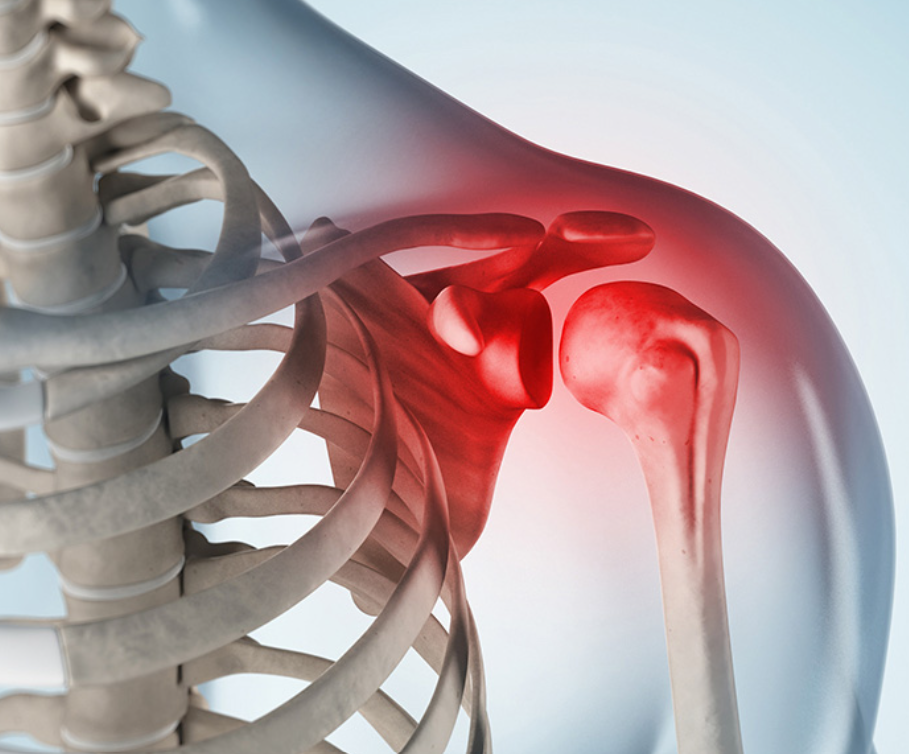

대부분 어깨 통증이 비슷한 경과를 보이는데 어깨 설회질 역시 초반에는 약한 통증에서 이후 참을 수 없을 정도의 통증으로 발전합니다. 이 때 통증의 양태는 어깨에 무거운 느낌에 더해 스치기만 해도 고통을 유발하며 어깨관절 앞쪽과 팔 아래에서 목까지 통증을 유발합니다. 아울러 급성으로 이러한 증상이 찾아오면 골절급의 통증이 나타나는 것이 특징입니다.

어깨 석회질은 화학적 종기라 부를 정도로 극심한 통증이 갑작스럽게 나타나는 경우가 많으며 어깨 인대 사이에 생성된 석회가 녹으면서 마찬가지로 엄청난 통증을 유발합니다. 이러한 통증은 어깨 석회질이 생기는 때 통증이 생기는 것이 아니라 녹을 때 주로 증상이 일어나기 때문에 분해기에 주로 큰 통증을 느끼게 됩니다.